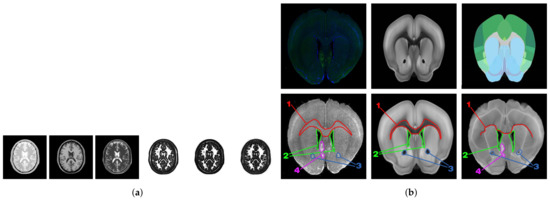

Most of the above modal transformation methods based on image representation are tested with T1-weighted, T2-weighted, and PD-weighted MR image data sets as the standard. Although the MR image data set is an image in three different modalities, its key features have a relatively simple correspondence and minimal noise interference. The modal transformation result of the ZMLD method with better performance is shown in Figure 1a. It can be seen from the figure that the modal transformation method can accurately extract the features of the three MR images and represent them to a unified modal. For the mouse brain slices (upper, left), namely the ATA (upper, middle) and ADA (upper, right) employed in this study, the specific morphological features are shown in the first row of Figure 1b, and there was a great difference in the corresponding key features between the original brain slices and the two kinds of the ARA. After the grayscale and affine transformation image preprocessing, the modalities between the grayscale brain slice (bottom, left) and ATA (bottom, middle) were closer, and they were selected for registration to use our approach without any processing. The results are shown in the second row and the three columns of Figure 1b. Regions 1, 2, and 3 in the brain slice images correspond to the ATA images, but the corresponding relationship of color features was very complex. Because of the inconsistency of this corresponding relationship and the difficulty of identifying boundary information, there is no unified standard for algorithm learning. Using the two non-unified modal images for training, the error correspondence was established, as shown in the second line (right) of Figure 1b. Moreover, the registration results were seriously affected by noise interference in the labeled region 4 in the brain slice. Owing to the differences in non-unified modality, more complex feature correspondence, and noise interference between the brain slice and ATA, conventional direct multi-modal image registration algorithms and existing image registration algorithms based on modal transformation made it difficult to realize the ideal regional localization.

Figure 1. (a) Multimodal MR images are often used in the study of modal transformation methods. The three on the left are T1-weighted, T2-weighted, and PD-weighted Magnetic Response Images; the three on the right are their result of modal transformation; (b) Display and registration of non-unified modal brain images. Top row: Brain Slice Image (left), ATA Image (middle), and ADA Image (right). Bottom row: The grayscale brain slice image (left, fixed) and the ATA image (middle, moving) were registered to generate the resulting image (right, moved). Among them, region 1 (red), region 2 (green), and region 3 (blue) represent corresponding features on different images, while region 4 (purple) represents neurons, which formed the image noise during the image registration process.